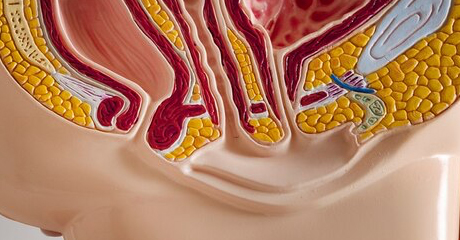

· Prolapso de Vejiga y Recto (Vejiga Caída)

· Prolapso Rectal

· Prolapso y Úlcera Rectal

· Rectocele